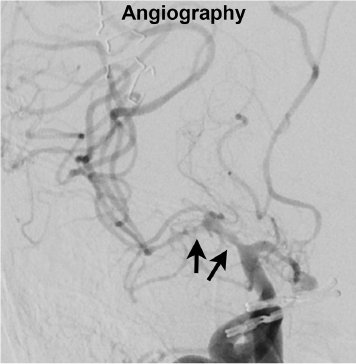

蛛网膜下腔出血后的血管痉挛CTP(CT灌注)影像 – CTP灌注图像的诊断性能评估 背景简要: 大脑血管痉挛通常会出现在破裂动脉瘤造成的蛛网膜下腔出血(SAH)之后,并引起迟发性脑缺血(delayed cerebral ischemic-DCI),DCI会造成更严重的神经机能和认知缺失。血管痉挛有可能发生在SAH之后的第2-14天内,所以尽早的探测/预测出现血管痉挛的这类病人,在治疗和病人预后管理中至关重要。CTP(CT灌注)影像能够提供多种定量的血流动力学信息,可用以监测早期血管痉挛。本试验利用CTP成像,评估了不同定量参数对SAH病人出现血管痉挛的诊断性能。 实验方法和重要结果: 在本试验中,从2011年3月到2014年5月一共纳入了26名因动脉瘤破裂引起的SAH病人(6.7±2.6天后),这些病人都在发现症状6小时内接受了CTP和DSA。其中10个动脉瘤位于前交通动脉,7个位于大脑中动脉,5个位于颅内颈内动脉,4个位于基底动脉上。每个病患都实施了动脉瘤弹簧圈和夹闭手术,其中10个病患具有多个动脉瘤。VPCT(CT灌注)扫描在40层Siemens Somatom AS CT上进行,造影剂团注和盐水追注速率为5mL/s。覆盖长度96mm,180mAs,80kV,以1.5s时间分辨率进行45s动态采集。层厚重建为10mm。定量参数CBF,CBV,MTT,TTD均由西门子公司去卷积算法得出。TTD被定义为TTS+MTT(起始时间+平均通过时间)。半自动图像分割,图像运动校正,大血管移除都由软件完成。动脉输入函数在大脑前动脉,静脉函数取为矢状静脉窦,然后进行计算。CTP图像参数CBF,CBV,MTT和TTD用以诊断是否出现因血管痉挛引起的灌注异常,每个责任血管灌注区域被两位神经影像医师独立评估,并划分为3分Likert量表(0分-无血管痉挛影响,1分-血管痉挛影响小于50%的血管灌注区域,2分-血管痉挛影响超过50%血管区域)。所有CT平扫已经呈现梗死的血管区域都被排除。第三位放射医师评估了DSA的16段颅内主要血管的3分Likert量表(0分-无血管痉挛影响血管直径,1分-血管痉挛影响小于血管直径50%的狭窄,2分-血管痉挛影响超过血管直径的50%)。在探测血管痉挛方面,如Table 2所示,ROC曲线分析发现TTD具有最高的诊断准确性(AUC面积0.832,敏感度0.737,特异度0.928),其次诊断性能较好的为MTT和CBF。TTD与MTT的准确性明显高于CBF和CBV。CBF的准确性高于CBV(Figure 1)。而TTD的探测血管痉挛的准确性与MTT无显著统计学差异,但是McNemar检验证实了TTD的敏感度要高于MTT。所有CTP定量参数指示的血管痉挛的严重性,均与DSA的结果相关。TTD与血管痉挛Likert分数的相关性最高(R=0.685),MTT仅次于TTD。所有CTP定量参数在Cohen Kappa检验中均显示出很好的一致性(inter-rater agreement 0.927 – 1.0)。 结论: 实验结果指示CTP的TTD参数具有最高的敏感度用以探测SAH之后的血管痉挛,并在评估血管痉挛严重性上与DSA最好的相关性。

Figure 1:58岁病患在动脉夹放置后第5天出现的血管痉挛(DSA)。CTP图像参数显示异常灌注出现于右侧MCA区域(TTD最为明显,CBV指示不清晰)。 原文Abstract: Introduction—In this study, we aimed to evaluate the diagnostic performance of different volume perfusion CT (VPCT) maps regarding the detection of cerebral vasospasm compared to angiographic findings. Methods—Forty-one datasets of 26 patients (57.5 ± 10.8 years, 18 F) with subarachnoid hemorrhage and suspected cerebral vasospasm, who underwent VPCT and angiography within 6h, were included. Two neuroradiologists independently evaluated the presence and severity of vasospasm on perfusion maps on a 3-point Likert scale (0—no vasospasm, 1—vasospasm affecting <50 %, 2—vasospasm affecting >50 % of vascular territory).A third neuroradiologist independently assessed angiography for the presence and severity of vasospasm on a 3-point Likert scale (0—no vasospasm, 1—vasospasm affecting < 50 %, 2—vasospasm affecting > 50 % of vessel diameter).Perfusion maps of cerebral blood volume (CBV), cerebral blood flow (CBF),mean transit time (MTT), and time to drain (TTD) were evaluated regarding diagnostic accuracy for cerebral vasospasm with angiography as reference standard. Correlation analysis of vasospasm severity on perfusion maps and angiographic images was performed. Furthermore, inter-reader agreement was assessed regarding findings on perfusion maps. Results—Diagnostic accuracy for TTD and MTT was significantly higher than for all other perfusion maps (TTD, AUC=0.832; MTT, AUC= 0.791; p<0.001).TTD revealed higher sensitivity than MTT (p=0.007).The severity of vasospasm on TTD maps showed significantly higher correlation levels with angiography than all other perfusion maps (p ≤ 0.048). Inter-reader agreement was (almost). perfect for all perfusion maps (kappa≥ 0.927). Conclusion—The results of this study indicate that TTD maps have the highest sensitivity for the detection of cerebral vasospasm and highest correlation with angiography regarding the severity of vasospasm.